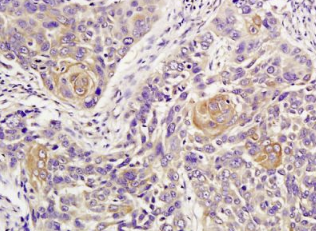

组织/细胞:人肺癌;4%多聚甲醛固定石蜡包埋;

抗原提取:柠檬酸缓冲液(0.01M,pH 6),15min煮沸,用3%过氧化氢阻断内源性过氧化物酶30min;37℃下阻断缓冲液(正常山羊血清)20 min;

孵育:抗ATM多克隆抗体,未结合(BS-1370R)1:300,4°C下过夜,然后与二级抗体结合,DAB染色。